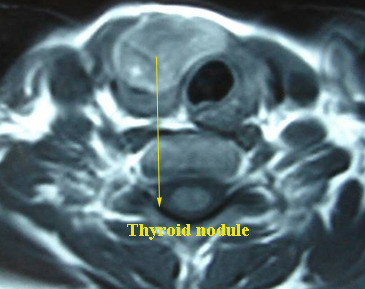

MRI scan: It plays a minor role in the evaluation of thyroid nodule. Its major advantage over CT scan is that contrast agent (gadoliunum) can be used without causing any interference to Radio nucleotide scanning.